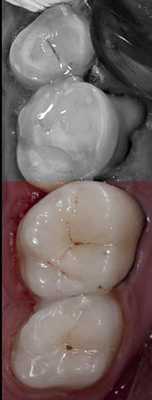

После восстановления и полимеризации дентинного слоя (Ceram•X™ duo+) один за другим были внесены оттенки основной и поверхностной эмали (Esthet•X® HD A2 и АЕ) общей толщиной 1,5—2 мм, тщательно адаптированы к поверхности с разметкой приблизительных контуров без последующего отверждения (рис. 6) .

Наступает очередь окклюзионного ключа (рис. 7) .

Для предупреждения возможного склеивания следует нанести на поверхность силикона небольшое количество адгезива. Ключ накладывается на зуб и медленно прижимается. После того как силиконовый оттиск встанет на свое место, нужно медленно его снять легкими раскачивающими движениями. Не следует торопиться и пытаться извлечь ключ одним рывком: это приведет к деформации композитного материала. Если все сделано правильно, порция неотвержденного эмалевого композита должна принять точную форму исходной жевательной поверхности (рис. 8) .

Излишки пломбировочного материала легко убираются брашиком. При возникновении каких-либо деформаций допускается повторная установка ключа. Далее проводится полимеризация в течение 30—40 секунд с учетом толщины композитного слоя (рис. 9) .